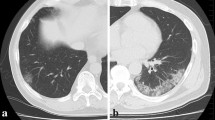

The software has the CE certification to document emphysema. The software provides automatic segmentation of the lungs and automatic segmentation and tracking of the airway tree. It provides the classification of voxels based on Hounsfield Units and a color-coded display of the segmented regions. We analyzed the CT scans by pre-setting a threshold value of Hounsfield Units in order to obtain a quantification for both lungs of emphysema ( − 1024/ − 977; blue) [20], of healthy residual lung parenchyma ( − 977/ − 703; yellow) [21, 22], of GGO ( − 703/ − 368; pink) and of consolidation (− 100/5; red) [21, 23,24,25] (Fig. 1). Chest CT evaluation using this computer tool was done on 116/134 (86.6%) patients because the software in 18 cases was not able to provide automatically quantification of thoracic disease.

Example of lung volumes calculated by computer-aided tool on CT images by pre-setting a threshold value of Hounsfield Units and a color in order to obtain a segmentation of both lungs and a quantitative evaluation of emphysema (− 1024/ − 977; blue), Healthy lung parenchyma (− 977/ − s703; yellow), GGO (− 703/ − 368; pink), consolidation (− 100/5; red) and other (− 368/ − 100; green)